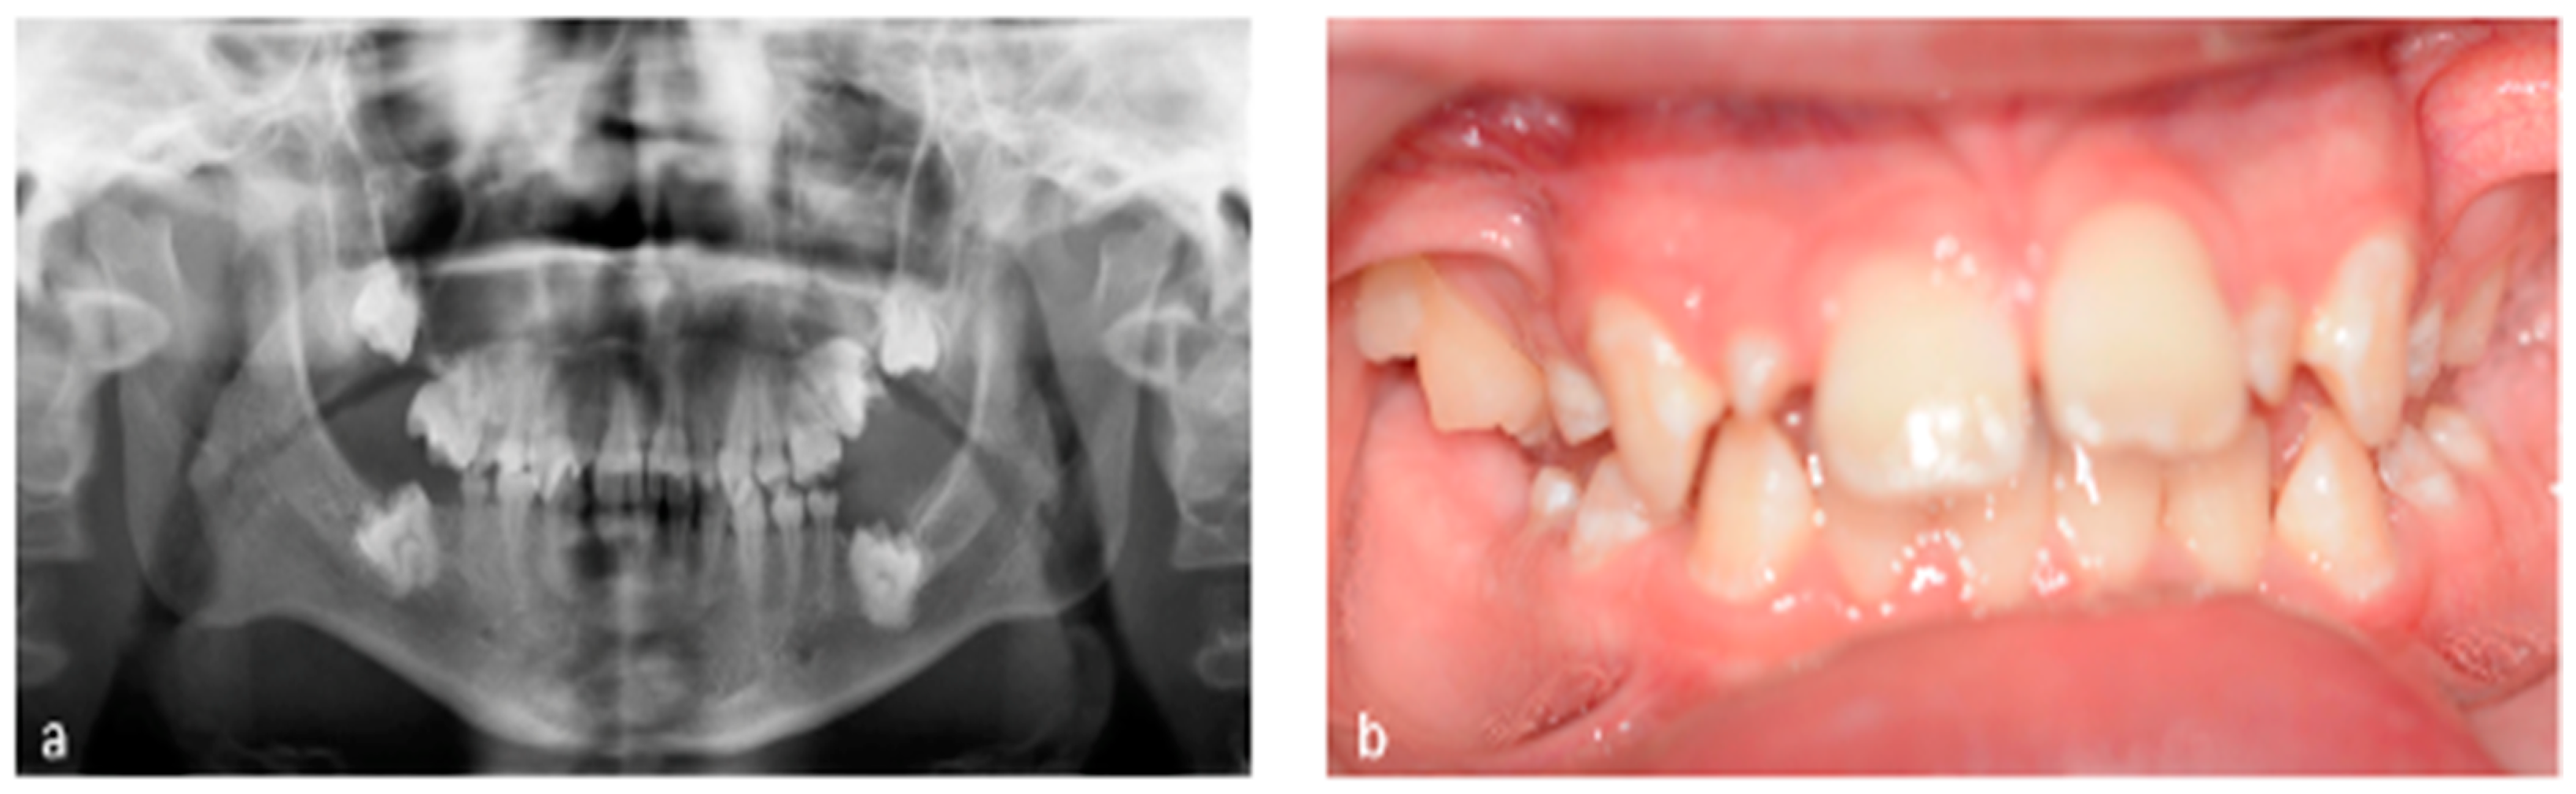

3.1. Tooth Development Disturbances